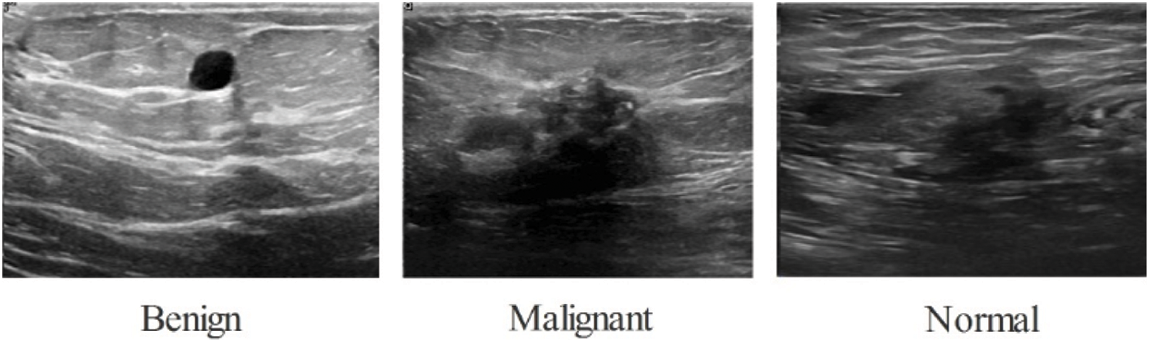

The BUSI database has been used in the study to validate the results. The package includes 780 photos with an aggregate file size of 500 by 500 pixels. As shown in Fig. 2 this information is categorized into three parts: normal (133 pictures), malignant (210 pictures), and benign (487 pictures). This original dataset was split into 50:50 training and testing groups. Following that, each class’s training photos were divided into three categories: normal (56 images), malignant (105 images), and benign (106 images) (243 images). Because this database [37] is insufficient to construct the deep learning method, a data augmentation phase is used.

Figure 2: BUSI dataset